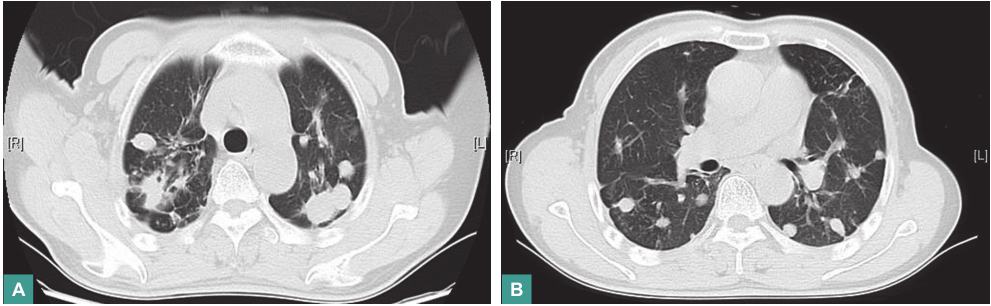

(4)影像学检查

胸部CT平扫和增强扫描示双肺弥漫多发结节及肿块,纵隔内气管前、腔静脉后部分淋巴结轻度增大(图1)。

图1 胸部CT表现

4.影像学检查

胸部CT显示双肺弥漫性多发结节和肿块,上肺部明显,局部病灶有小空洞,纵隔内淋巴结无明显肿大,增强扫描显示肺内病灶无明显强化。

行抗结核治疗1年后,复查胸部CT示双肺病灶明显吸收(图7)。

图7 抗结核治疗1年后胸部CT表现